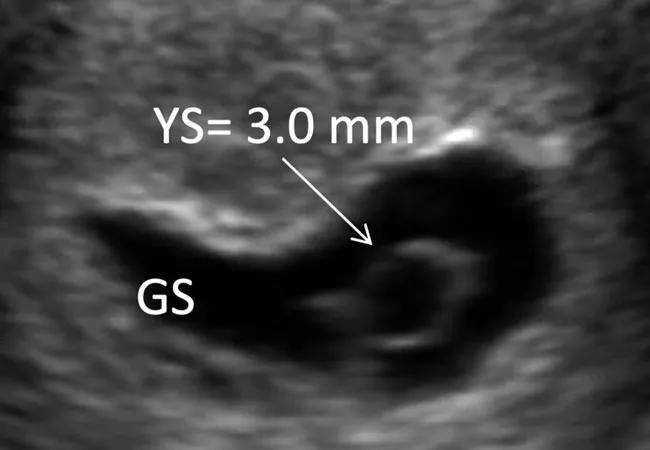

To develop a predictive model for early pregnancy loss, Dr. Detti used transvaginal ultrasound (TVUS) to measure the gestational sac (GS), yolk sac (YS), crown-rump length (CRL) and heart rate (HR) in first trimester patients (N = 252) who had been fertility patients. TVUS was conducted serially in singleton and twin pregnancies from gestational weeks 6–10.

In pregnancies that will be lost, GS, CRL and YS are the first TVUS measures to become abnormal, with HR becoming abnormal later, closer to the time of loss. In pregnancies that continued beyond the first trimester, the YS grew 0.38 mm per week, the GS diameter grew 6.65 mm per week and CRL grew 7.56 mm per week. Compared to continuing pregnancies, these TVUS markers began to differ significantly at some point in the first 6–9 weeks.

“Of all markers, the YS is probably the most important. When the YS is bigger than it should be for a specific gestational age, the pregnancy will probably be miscarried in the first trimester,” Dr. Detti explains.

In this study, YS was the strongest predictor of miscarriage, and its size predicted loss seven days prior to its occurrence. In weeks 7 and 8, a larger median YS was associated with increased risk of loss. In contrast, a smaller median YS diameter was associated with increased risk of pregnancy loss.

At 8 weeks, a smaller than expected GS predicted loss. Median GS was 15 mm in pregnancy losses and 31 mm in continuing pregnancies. CRL was significantly larger in sustained pregnancies from weeks 6-10. HR began to diverge significantly among the two groups between 7 and 8 weeks of gestation, with pregnancies destined for loss increasing only 3 BPM compared to 13 BPM in continuing pregnancies.

Ultrasound and hysteroscopic images of the yolk sac in a partial mole pregnancy (Karyotype: 69, XXY at microarray analysis)

(A) Ultrasound picture showing an enlarged yolk sac at 6 weeks and 1 day of gestation. (B) Ultrasound picture showing an enlarged yolk sac at 8 weeks and 2 days of gestation. (C) Hysteroscopic view of the yolk sac at the time of pregnancy evacuation at 8 weeks and 2 days of gestation, after embryonal demise. (D) A portion of the yolk sac can be noted just outside of the amniotic sac, with the embryo within it, in the background. Images used in compliance with the Creative Commons Attribution 4.0 International License. Originally published here: Detti L, Francillon L, Christiansen ME, et al. Early ultrasound measurements and prediction of first trimester loss: a logistic model. Sci Rep. 2020:10;1545.